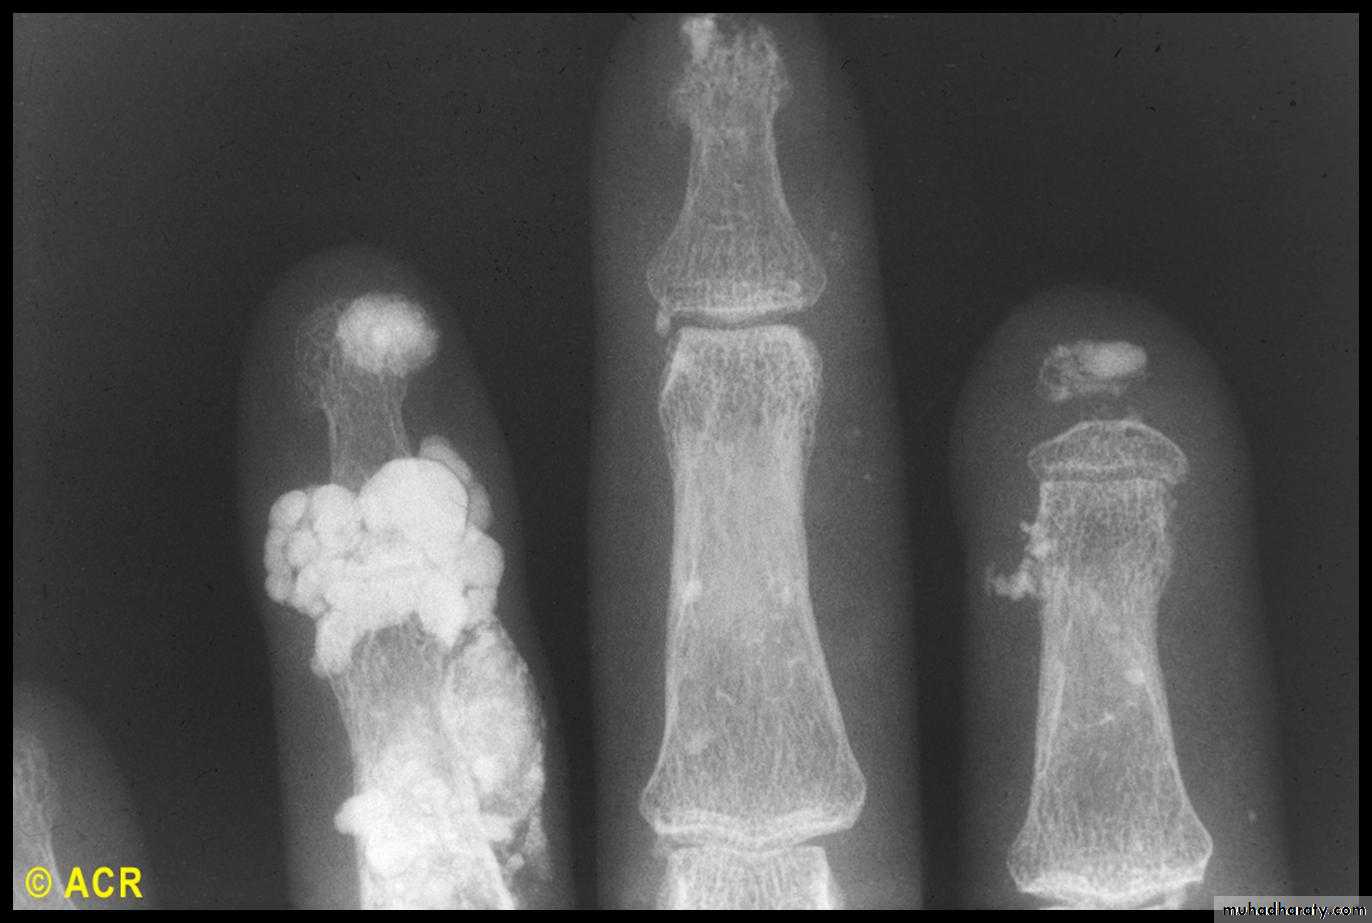

Many patients with LCSS have features that are phenotypically grouped into the ‘CREST’ syndrome (Calcinosis, Raynaud’s, Esophageal involvement, Sclerodactyly and Telangiectasia).

Initially, there is nonpitting oedema of fingers and flexor tendon sheaths. Subsequently, the skin becomes shiny and taut, and distal skin creases disappear.

Skin involvement restricted to sites distal to the elbow or knee (apart from the face) is classified as ‘limited disease’ or CREST syndrome . Involvement proximal to the knee and elbow and on the trunk is classified as ‘diffuse disease’.

This is a universal feature and can precede other features by many years.Involvement of small blood vessels in the extremities may cause critical tissue ischaemia, leading to skin ulceration over pressure areas, localized areas of infarction and pulp atrophy at the fingertips.

Musculoskeletal features

Arthralgia, morning stiffness and flexor tenosynovitis are common.Restricted hand function is due to skin rather than joint disease and erosive arthropathy is uncommon.